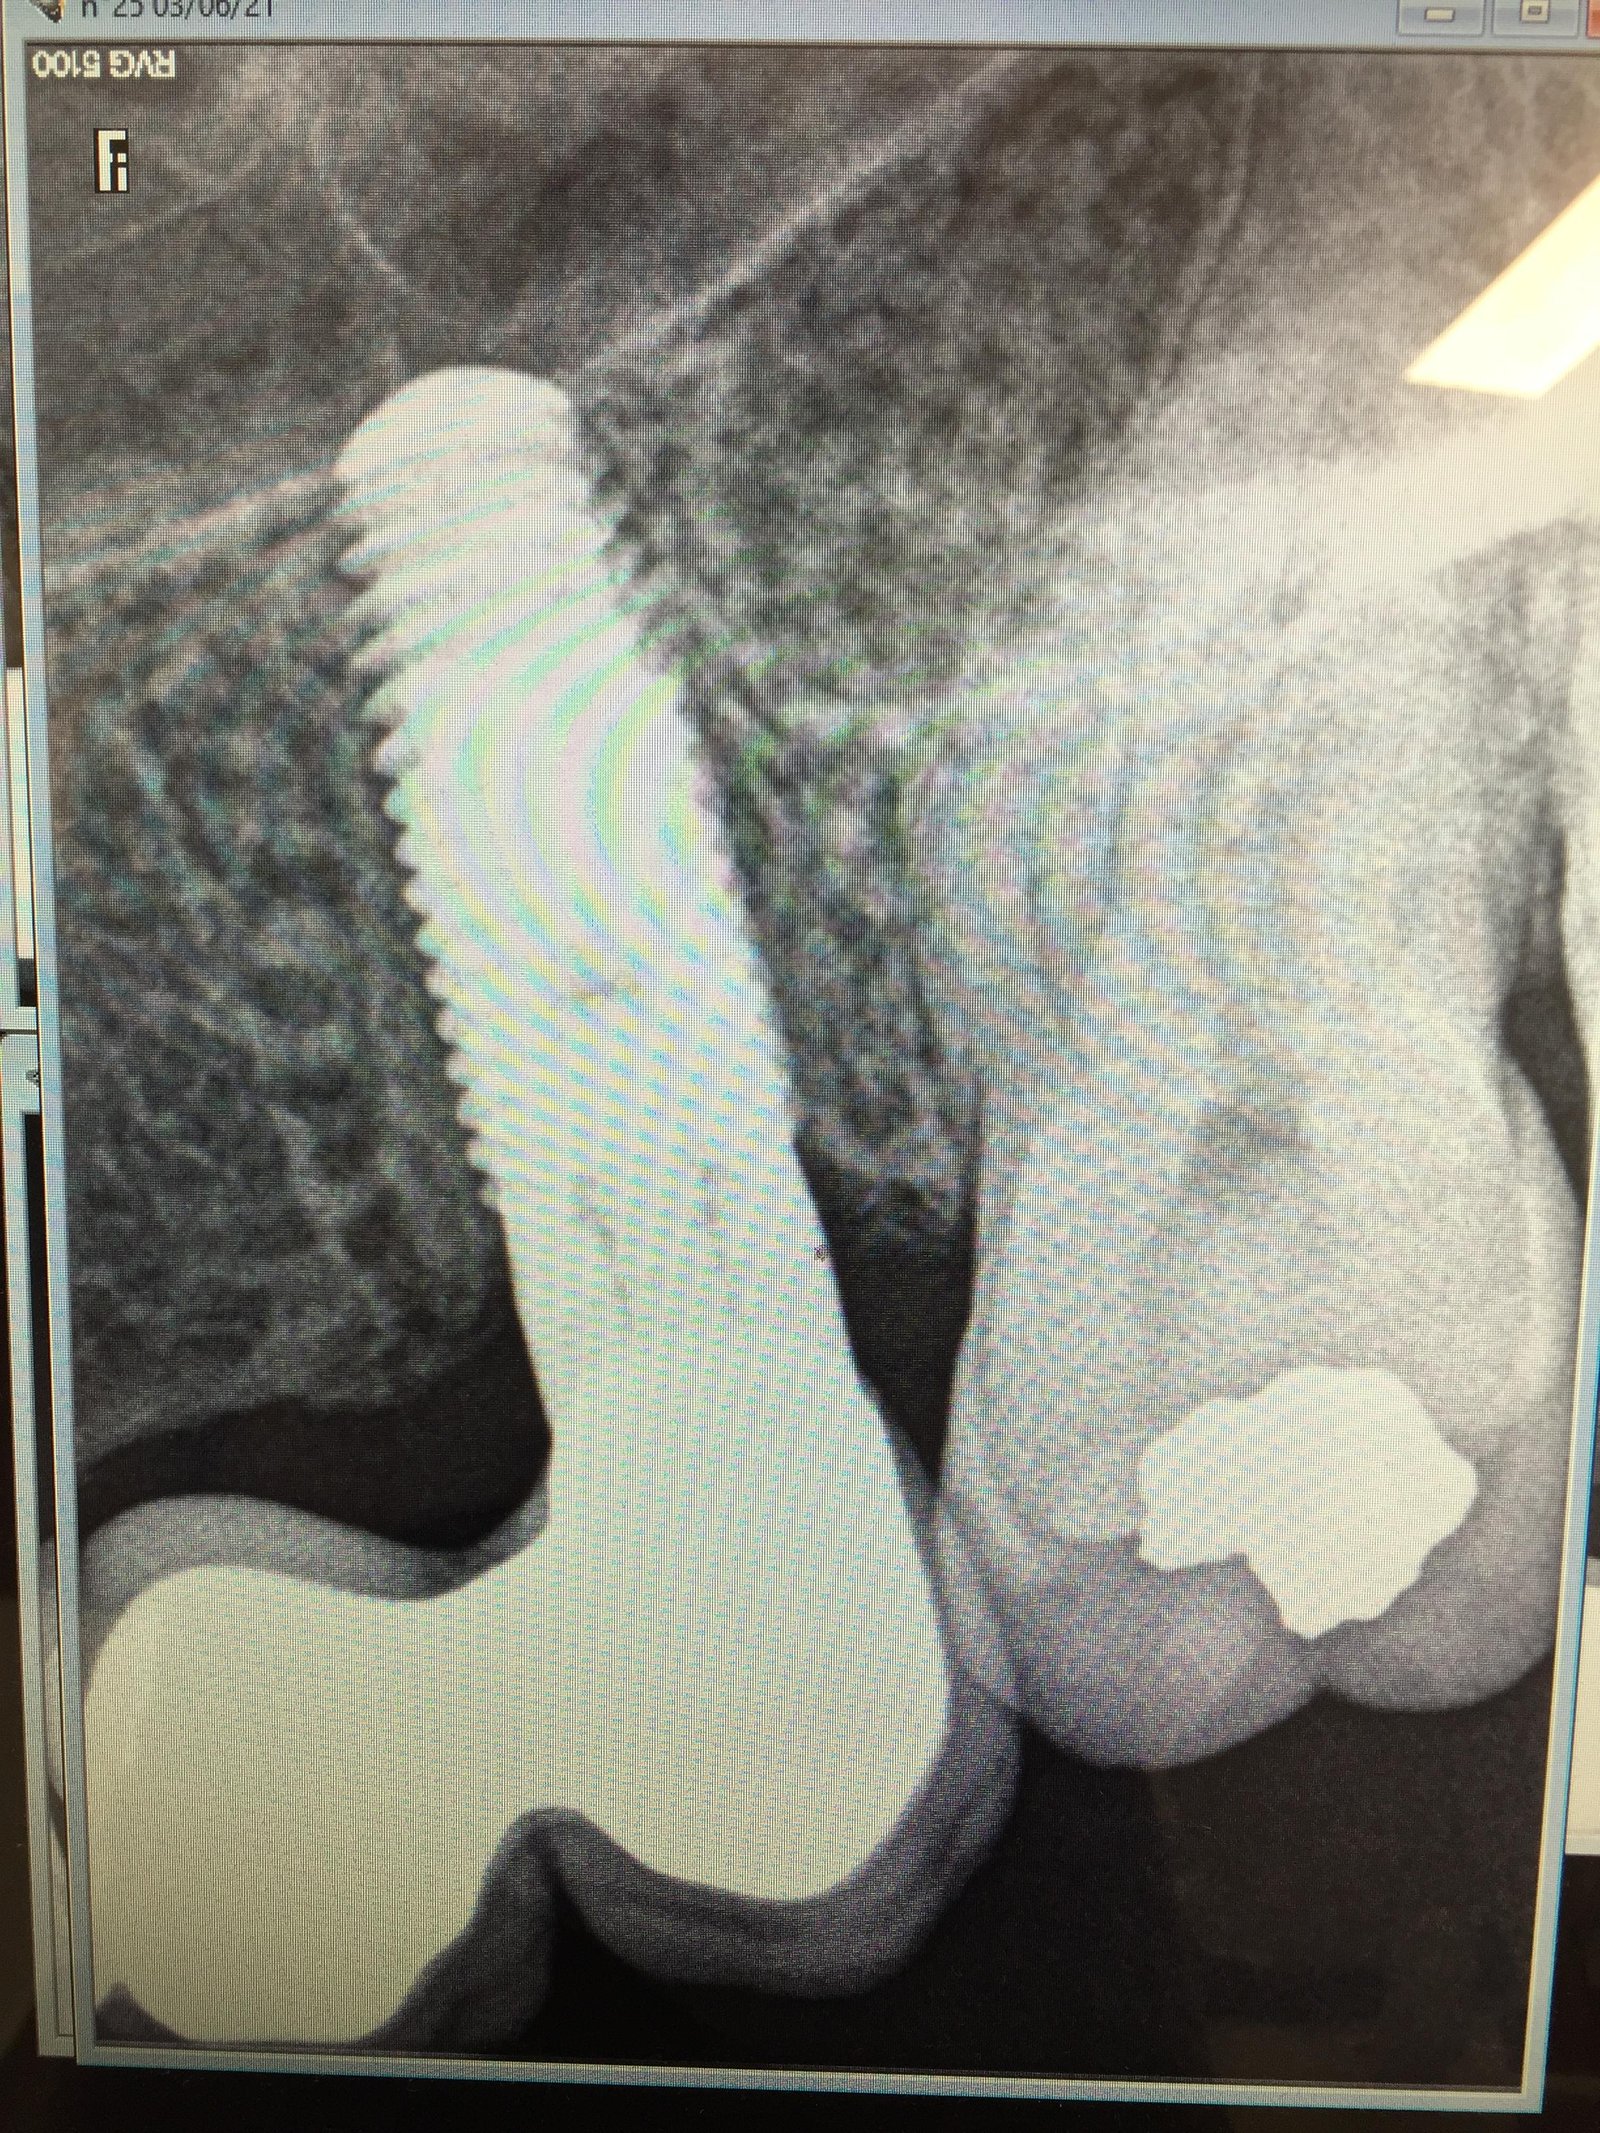

El implante que nos mandas, es un zimmer TSV de plataforma 4.5 mm morada. Es una conexión hexagonal interna.

Si por algún casual vieras que es de color verde, aunque no lo creo, sería de plataforma 3.5 mm.

Muchas gracias David.Al levantar la corona no he visto la plataforma morada es plateada mira la imagen.Sigue valiendo el coping de

Entonces es el modelo antiguo. De ahí que sea sin color. Con todo y con eso es un TSV de zimmer de plataforma 4.5 mm sin duda.